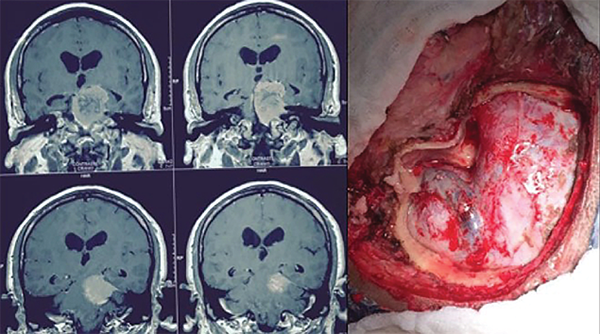

Figura 4: RM coronal con gadolinio que muestra tumor con componente en la fosa posterior y en la fosa media. Caso ideal para el abordaje petroso, también conocido como petrosectomía posterior o abordaje presigmoideo supra/infratentorial (izquierda). Visualización del abordaje antes de abrir la duramadre (izquierda).

Figura 7: Meningioma petroclival grande resecado por abordaje suboccipital. Se observa un pequeño componente tumoral que se extiende en la fosa media en continuidad con el tentorio. Esta parte tumoral se resecó abriendo el tentorio a través de la fosa posterior. No se resecó una pequeña extensión en el seno cavernoso.